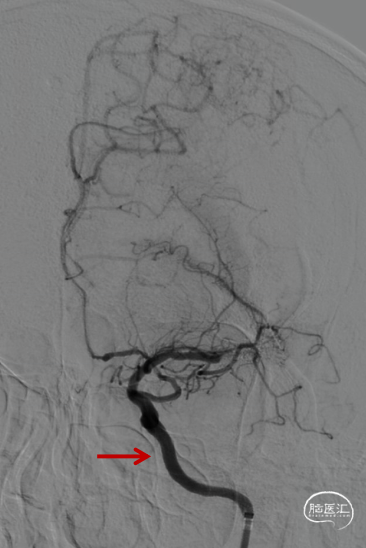

术前造影提示左侧颈内动脉自起始部闭塞,前交通动脉开放,同侧大脑前动脉及大脑后动脉皮层对左侧半球形成皮层侧支代偿。

微导管微导丝配合下多次尝试通过颈内动脉起始部闭塞段未能成功,在125mm多功能导管配合下,将微导管及Command微导丝成功越过颈内动脉起始部闭塞段,微导管造影确认在颈内动脉真腔,但远端未见显影,考虑血栓所致。静脉推注替罗非班8ml,并以6ml/h持续泵入。